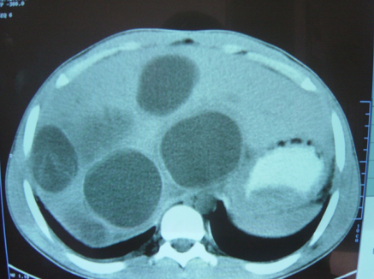

Baddi-Kiari sindromu böyük qaraciyər venalarının tıxanması nəticəsində meydana gələn venoz durğunluqdur, qaraciyər venaları ilə yanaşı aşağı boş venada da tıxanma ola bilir. Tromboz, fibroz, membran və infiltrasiya (şişlər, iltihab) ən çox rast gələn səbəbləridr. Erkən mərhələlərdə kəskin hepatit və kəskin qaraciyər yetməzliyi, xroniki mərhələdə sirroz və PH meydana gələ bilir. Diaqnozu üçün tomoqrafiya və kontrastlı angioqrafiya lazım gəlir, Qc venalarının trombotik tutulması diaqnozu təsdiqləyir. digər xarakterik əlaməti birinci seqmentin hipertrofiyasıdır. Erkən mərhələdə dekompressiya (cərrahi və stend) sirroz əmələ gəldikdə isə transplantasiya ön planda tutulur.

Qaraciyər venalarının görünməməsi, kontrastlaşmaması və ya trombla tıxanması.

- Görüntüləmədə qaraciyər venalarının tıxanması, I seqment hipertrofiyası ola bilər (xroniki forma);